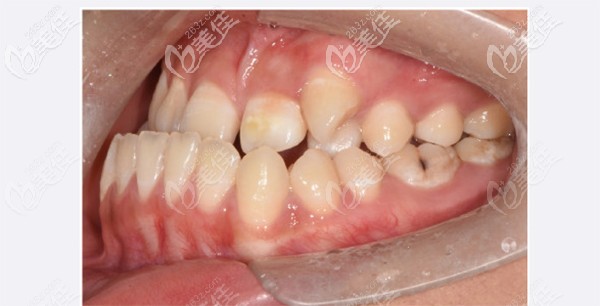

正常咬合是上前牙盖过下前牙大概三分之一左右,对刃是指上下前牙切端,没有覆合、覆盖的关系。看看我家孩子的牙齿情况,你就了解了。

在石家庄全博口腔医生给我讲,对刃也是一种轻度反颌的表现,不仅影响面容,还有咀嚼功能也会降低,咬合磨耗过大受损等。

然后给孩子拍了CT后,症状就更加明显了。下颌突出,明显看出有地包天的情况。